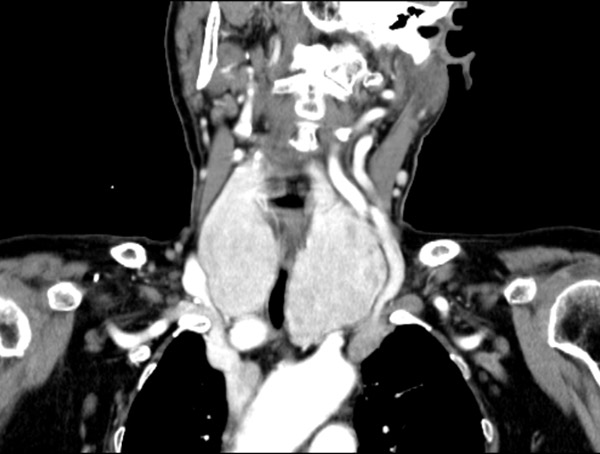

睡觉不能平卧,走路仅10步之内 患者石阿姨79岁,平时就气短乏力,反酸烧心,活动受限。近3个月症状加重,睡眠已经不能平卧,走路仅十步之内,严重影响日常生活。 石阿姨来沈阳市第十人民医院(沈阳市胸科医院)就诊,经检查后诊断为“胸骨后巨大甲状腺肿”、“食管裂孔疝”,胸骨后巨大的甲状腺肿压迫气管,导致气道严重狭窄, 呼吸困难。为解决石阿姨的痛苦,决定手术治疗,入住普外科后经完善检查,术前诊断结果很不乐观: 1. 胸骨后巨大甲状腺肿,气道狭窄;2.食管裂孔疝(Ⅲ型),胃食管反流病;3. 慢性阻塞性肺疾病(COPD);4.冠心病、高血压。 石阿姨高龄、肥胖且基础病多,影像学及内镜显示,声门下约2.5cm处气管出现长约3cm的严重狭窄,最窄处约3mm。甲状腺下极达主动脉弓以下,压迫双侧无名静脉及头臂干并向大血管间隙生长。麻醉和手术面临巨大风险。 多学科会诊,万全之策为手术护航 普外科向医务部提交多学科会诊,由麻醉专家庄晓晨副院长牵头组织普外科、麻醉科、胸外一科、呼吸二科、心脏中心各位专家进行科学严谨的全面评估,多学科会诊意见:要想解除气道狭窄缓解呼吸困难,只有手术切除甲状腺肿,食管裂孔疝二期处理,并制定了围手术期治疗措施及详细的麻醉、手术预案。 麻醉科根据此患者特殊情况拟定两种麻醉方案, 方案一:局麻下行气管镜探查,如狭窄处条件允许,则清醒状态下置入合适管径插管后予以全身麻醉。 方案二:如气管镜探查狭窄处口径过窄,无法置入合适气管插管不能满足通气需要,则行ECMO(体外人工膜肺)辅助下全麻手术,即于左右股静脉分别置入一根导管至下腔静脉与右心房处,将患者静脉血从下腔静脉抽出后经氧合器氧合再泵入右心房的方式来代替肺脏工作,从而达到无需气管插管又能满足机体氧供的效果。 普外科也制定了手术预案:1.甲状腺肿巨大,同重要血管神经关系密切,术中精细解剖,逐次支持切除,避免血管损伤至大出血,并要求快速切除病变解除气道压迫。2. 如逐次支持不能切除甲状腺肿,行劈开胸骨切除或胸腔镜下解剖游离甲状腺下极。3.气管长期受压,有气管软化可能,切除甲状腺肿可致气管塌陷,如不能悬吊支持气管,行气管切开气管套管置入。与患者及家属充分沟通并告知风险后,其表示十分理解与信任并坚决要求在我院行手术治疗。 巨大甲状腺肿2小时全切除,气道压迫完全解除 手术当日,麻醉科主任王涛、副主任医师张祥超等麻醉团队将各种型号导管、紧急气道装置、ECMO设备准备就绪,虽然插管过程困难,但最终在患者清醒状态局麻下经气管镜将较细的6.5#插管成功送至狭窄处远端后予以全身麻醉,连接呼吸机管路顺畅,压力适中且氧合良好。普科主任陈晓峰、副主任医师王鑫、主治医师刘聪手术团队在手术室护理团队的配合下,精细解剖、逐次支持切除,2个小时完成胸骨后巨大甲状腺肿双侧次全切除,完全解除气道压迫。术后第一天,阿姨下床活动行走自如,5天出院,彻底告别了不能平卧、轻微活动就呼吸困难的生活。 这例手术的成功,体现了医院多学科团队鼎力协作的专业风采。在ECMO技术支持保障、充分术前预案的基础上,即便面对复杂的疾病,也有确切实力为越来越多的患者解除病痛。 在沈阳市第十人民医院(沈阳市胸科医院),医者不仅有严谨的专业能力,更有为患者解除病痛的信念,与病魔做斗争、与患者同呼吸,为更多家庭造福。 供稿:普外科 普外科 科室简介: 沈阳市第十人民医院(沈阳市胸科医院)普外科为集医疗、科研、教学为一体的综合性临床科室。主要收治甲状腺、颈部肿物及乳腺疾病,肝胆胰脾、胃肠、肛门疾病,食管裂孔疝、腹外疝等,疾病涵盖感染、肿瘤及创伤等。以微创治疗为主要治疗手段,患者创伤小,恢复快。 联系电话:88323438转8228 地址:沈阳市第十人民医院 一号楼10层